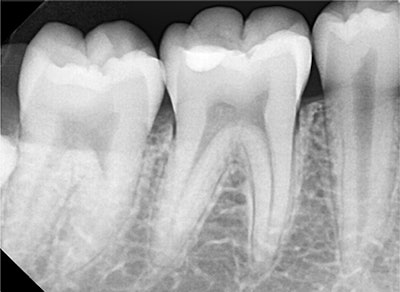

The intraoral periapical radiograph shows radiopaque restoration of the mandibular right first molar involving the enamel and the upper one-third of the dentine. The radiograph does not show any pulpal or periapical pathology.